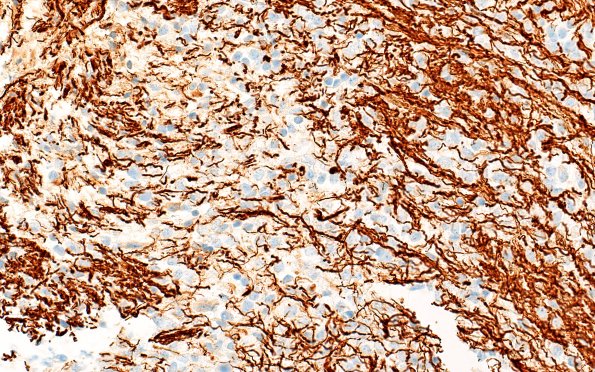

Washington University Experience | NEOPLASMS (GLIAL) | Diffuse midline glioma, H3 K27-altered | 16C DMG (Case 16) NF 20X

Neurofilament confirms the presence of entrapped axons, consistent with an infiltrative growth pattern of the tumor. (NF IHC)